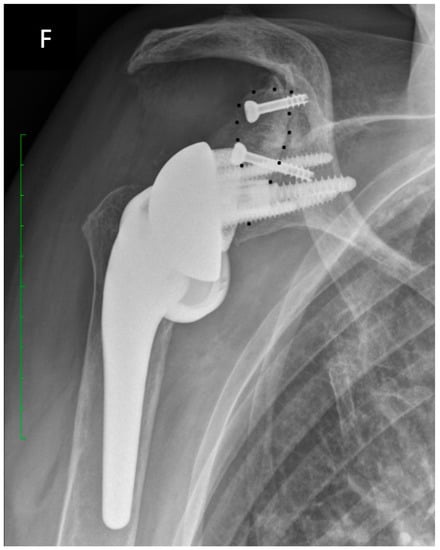

2.2. Surgical Technique and Implant Design